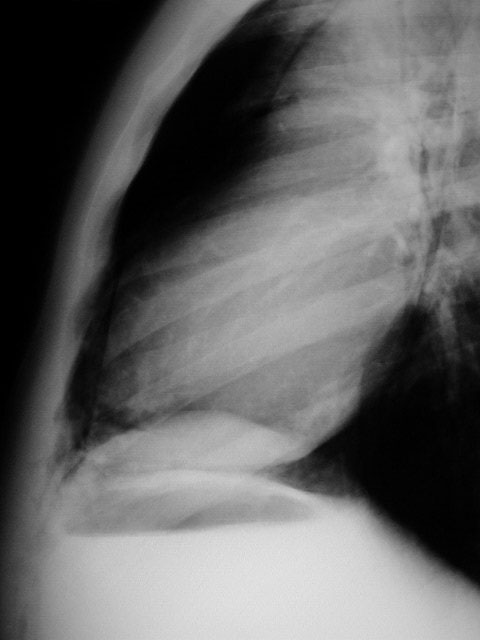

En la radiografía lateral de tórax puede verse la arteria pulmonar (flecha roja) rodeada de aire. También puede verse aire delimitando la raíz aórtica (flecha blanca).

Es un signo de neumomediastino visible en la radiografía lateral de tórax. El aire extrapulmonar rodea la porción mediastínica (extrapericardial) de la arteria pulmonar derecha produciendo un anillo hipodenso alrededor de ésta.